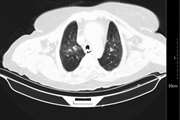

گزارش یک مورد نادر از تجمع مایع اطراف قلب ناشی از COVID-19 با تشخیص اشتباه به عنوان لخته خون در ورید گردن

تورم گردن و تنگی نفس در بیمارهای ویروسی ممکن است ناشی از بیماریهای کمتر شناختهشدهای مثل تجمع مایع اطراف قلب (افیوژن پریکاردی) باشد که با بیماریهای رایجتر مثل لخته خون ورید گردن اشتباه گرفته میشود. درمان نادرست میتواند بسیار خطرناک باشد. پزشکان باید قبل از شروع درمان رقیقکننده خون، با استفاده از روشهای دقیق تشخیصی مانند تصویربرداریهای قلبی و ریه، تشخیص را تایید کنند تا از عوارض جدی جلوگیری شود.